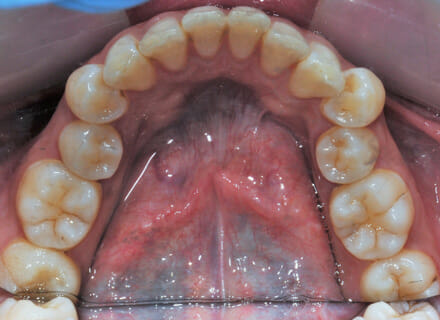

This lady came to us because she said she was goofy – her front teeth were sticking out. In the lower jaw, the teeth didn’t have enough room so 2 teeth had been pushed out of the bite altogether. We fitted a clear brace and were able to reduce the overbite by 80%. We also managed to pull the lower premolars back into the arch. This lady did not require any extractions. She was so pleased with the results especially as no healthy teeth were removed!